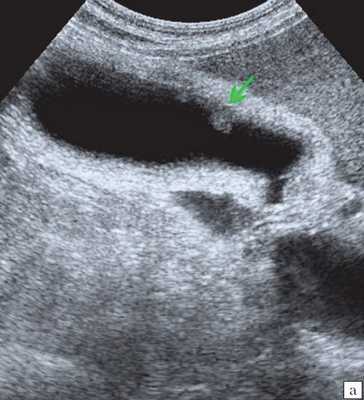

Ультрасонография является эффективным средством выявления полиповидной формы холестероза 7. Традиционной считается следующая сонографическая характеристика холестериновых полипов: неподвижные гиперэхогенные структуры, которые не дают акустической тени и прикрепляются к стенке желчного пузыря. Контуры таких образований, как правило, ровные, а размеры таких образований различны, чаще не превышают 10 мм (рис. 2).

a) Одиночный полип в желчном пузыре (гиперэхогенное пристеночное неподвижное образование, с ровными контурами, без акустической тени).

б) Одиночный полип в желчном пузыре.

Мелкие холестериновые включения, образующие диффузную сеточку в толще подслизистого слоя размерами 1-2 мм, выглядят как локальное утолщение или уплотнение стенки желчного пузыря и в некоторых случаях (см. рис. 2) вызывают реверберацию (эхографический симптом "хвост кометы").